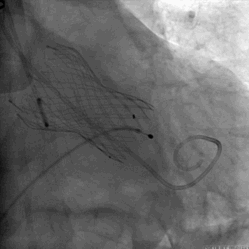

跨瓣DSA